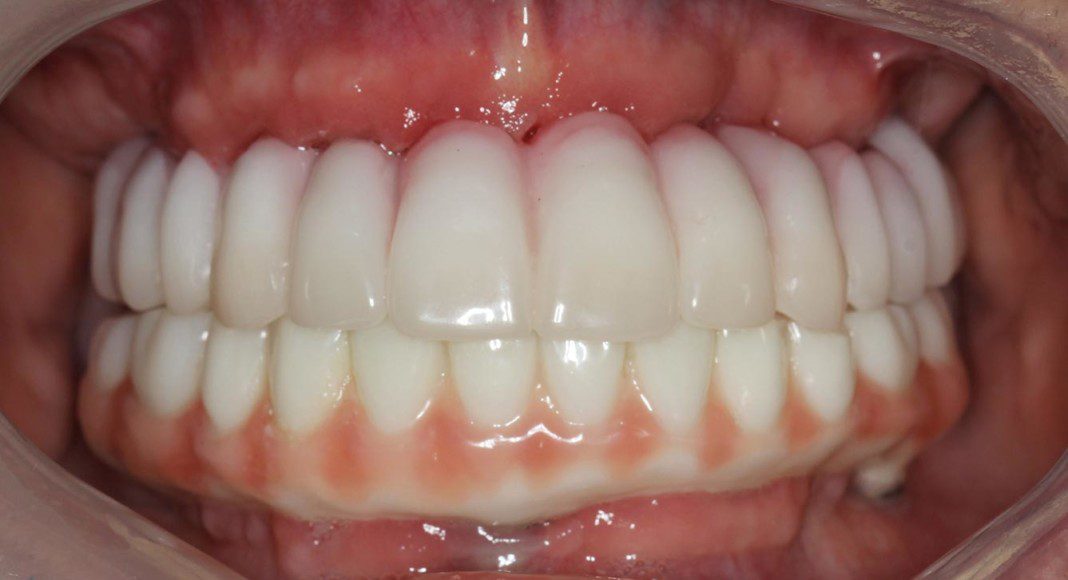

New upper and lower temporaries are fabricated and are retained by only the implants as there are no natural teeth remaining.

Two months later, after implant and gum tissues are ready, impressions are made and a wax mock-up tried in the mouth. This is where the dentist, the patient and any family members whose opinions count Wax, mock-up on model. This is the appointment where the dentist, the patient and any family members whose opinions count are encouraged to critique the appearance of the teeth. We evaluate the color, length, width, smile, non-smiling appearance, overall arch form and appearance while speaking. No stone is left unturned as this will be the last time the teeth can be changed. If are necessary, another try-in of the mock-up is completed.